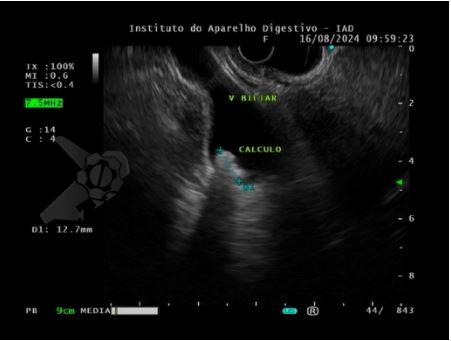

- Vesícula biliar normodistendida, com paredes finas, exibindo imagem hiperecóica e móvel, formadora de sombra acústica posterior, medindo cerca de 12 mm no maior eixo, compatível com cálculo (Foto 1);